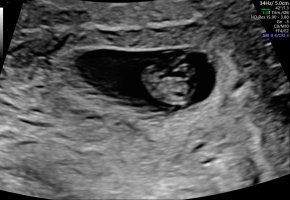

Innvendig. Best å se så tidlig med innvendig ulSå godt å se <3 Er det utvendig ultralyd?![]()

Lille vennEt lite blinkende hjerte med god hjertelydEr i uke 7, så mellom 7+4 og 7+5 er riktig enda. Hun målte lille til 1 cm, men hun gjorde det så fort, så ikke sikkert det stemmer.